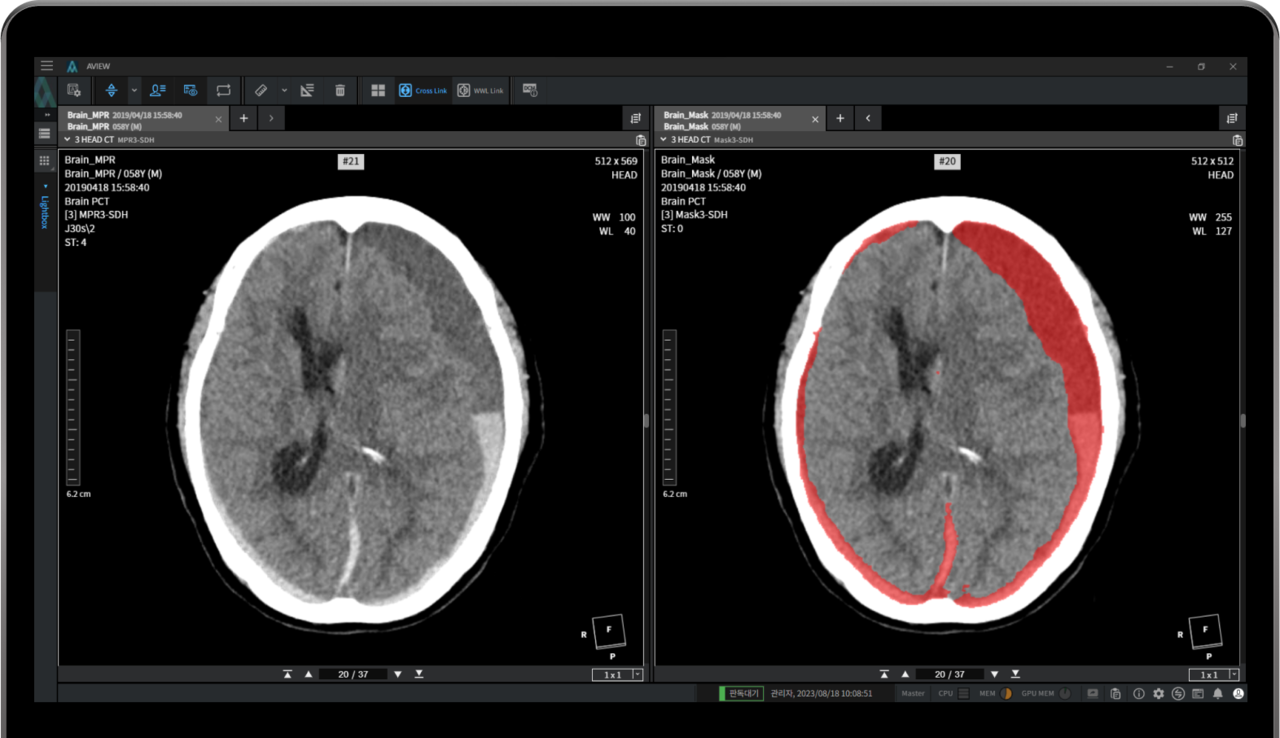

에이뷰 뉴로캐드는 뇌출혈 뇌 영상 검출-진단 보조 소프트웨어다. 기술 혁신성과 신규 시장 창출 가능성 등을 인정 받아 지난 해 식품의약안전처와 보건복지부 주관 혁신의료기기 통합심사 평가를 통해 혁신의료기술로 선정됐다. 선별 급여 혹은 비급여 방식으로 의료 현장에서 사용할 수 있게 된 제품이다.

특히 환자 CT 이미지를 기반으로 제한된 시간 내 영상을 판독, 진단-치료 결정까지 할 수 있도록 지원한다.

주요 기능으로는 ▲출혈이 많은 영상부터 환자군 정렬 ▲출혈량에 따른 우선 병변부 정보 제공 ▲뇌출혈 의심 부위 미리보기 기능을 통해 응급환자에 대한 판독 우선순위도 제시할 수 있다. 또 2D와 3D 영상을 비교할 수 있고 의료기관의 판독시스템(PACS)과도 연동할 수 있다.